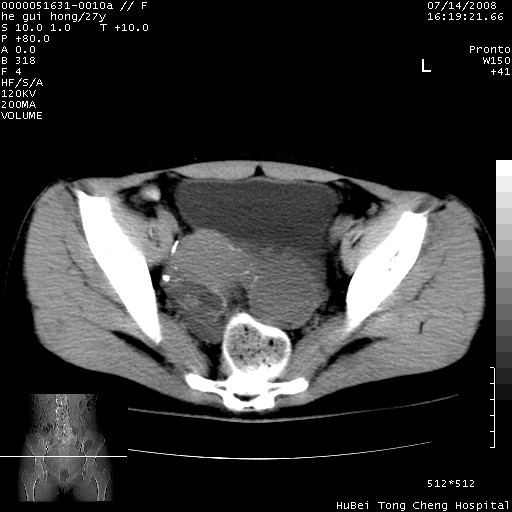

以下是引用杀毒软件在2008-7-20 8:03:00的发言:[br]支持双侧卵巢囊腺瘤可能性大!

以下是引用zjzjr在2008-7-20 13:36:00的发言:[br]双侧附件囊腺瘤可能性大!